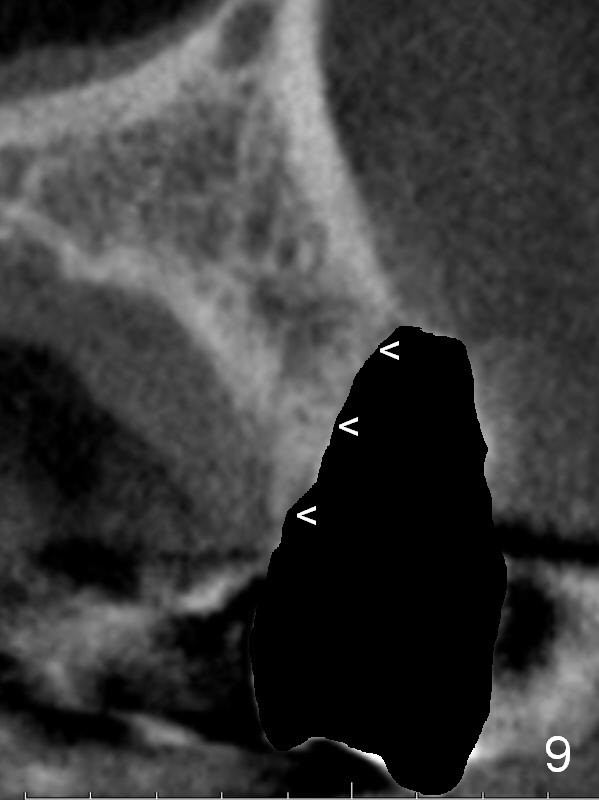

A 4.5x14 mm bone-level or 4.5x17 mm tissue-level implant appears to be appropriate for the site according to the PA (Fig.6,7). CBCT shows that there is enough bone to place a 4.5x20 mm tissue-level implant (Fig.8). This is more appropriate, considering the large radiolucency (Fig.5), the age of the patient (possibly osteoporosis), and the maxilla (bone softer than that of the mandible). The implant will be supported by approximately 8 mm solid bone apically (Fig.8).

In addition, osteotomy will be under prep. The depth of a 2 mm pilot drill, 2.5 mm and 3 mm reamers will be 20 mm, 17 mm and 14 mm, respectively. A 4.5x20 mm tap will be inserted 17 mm before placing the corresponding implant. Intraop PAs are to be taken following the pilot drill, tap and implant.

After extraction, the bottom of the socket must be oblique (Fig.9 arrowheads). As usual, osteotomy is initially at the junction of palatal (Fig.10 P) 1/3 and middle 1/3 perpendicular to the plate. Once the drill gets engaged, the trajectory is to be changed (Fig.11 curved arrow) so that the apical end of the osteotomy (red line) is as close to the buccal plate (B) as possible. The purpose is to keep the palatal end of the osteotomy as palatal as possible. In spite of the effort, an angled abutment is expected, as large as 20 degree (Fig.8 purple angle).

After preparation of the implant and abutment and fabrication of an immediate provisional, a cone-shaped Osteo-tape (Fig.8 orange outline) is inserted against the buccal socket wall (most likely completely soft tissue), followed by bone graft (red circles, to the level of the palatal crest (>)).